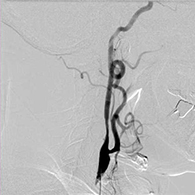

もやもや病に対する頭蓋内外脳血行再建術

もやもや病は原因不明の進行性脳内血管狭窄疾患であり、国によって難病指定されている病気です。典型的には小児や若年成人に起こり、脳虚血(脳梗塞)、脳出血を生じます。頭蓋内外脳血行再建術(バイパス手術)が必要な場合があります。

38歳、もやもや病、左半身一過性脳虚血発作

<画像所見>

(脳血管の脱落、赤丸部)

<術後画像検査>

術後はバイパス血管が脳内に向かって出現している(赤丸印)。